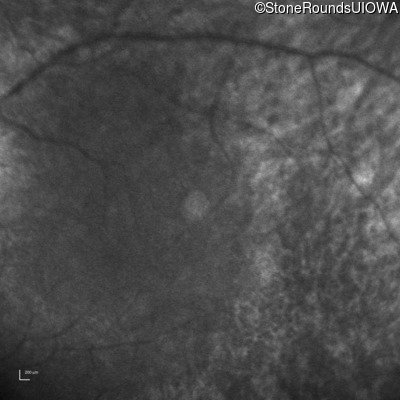

Infrared Fundus Photograph - Right -

No Light Perception

Exemplar

Expanded OCT Stack

×

Infrared Fundus Photograph - Left -